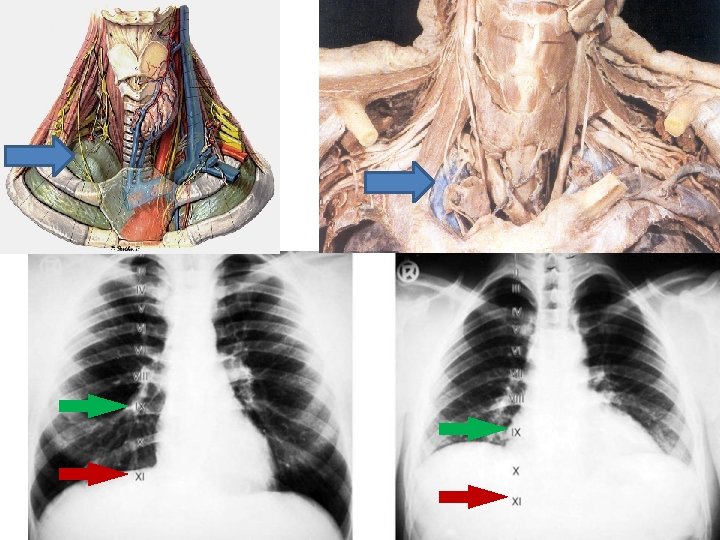

Trachea Pars cervicalis C 6 -Th 1 Pars thoracalis Th 1 -Th 5 Länge: 10 -13 cm Paries membranaceus Sie liegt an der Vorderfläche des Ösophagus Sulcus oesophagothrachealis Bronchus principalis dexter et sinister Bifurcatio et Carina thracheae

Tracheotomie Im Atemnot (aspirierter Fremdkörper, Kehlkopf-Ödem, beidseitige Rekurrensparese, usw. ) – Tracheotomia superior: bei Erwachsenen über dem Isthmus der Schilddrüse (2. -4. Tracheaknorpel); – Tracheotomia inferior: bei Kindern unter dem Isthmus der Schilddrüse; Gefahr: wegen Venenplexus der V. thyroidea inf. und der tiefen Lage der Trachea

Normales Röntgenbild des Thorax